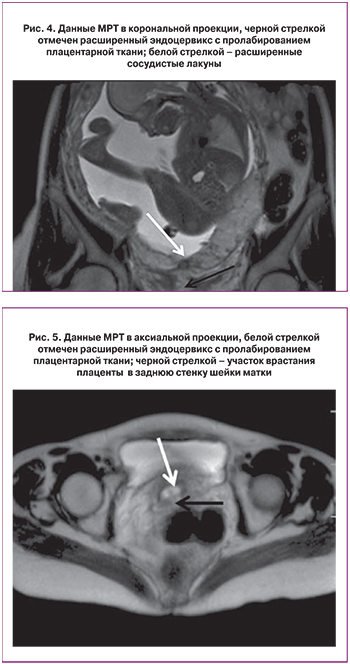

По данным проведенной МРТ, также установлено наличие полного предлежания плаценты, не исключается врастание в область внутреннего зева: «в нижнем сегменте матки, шеечно-перешеечной области, преимущественно парасаггитально справа визуализируются участки патологического МР-сигнала, округлой формы (сосудистые лакуны) и расширенные извитые сосуды» (рис. 4,5).